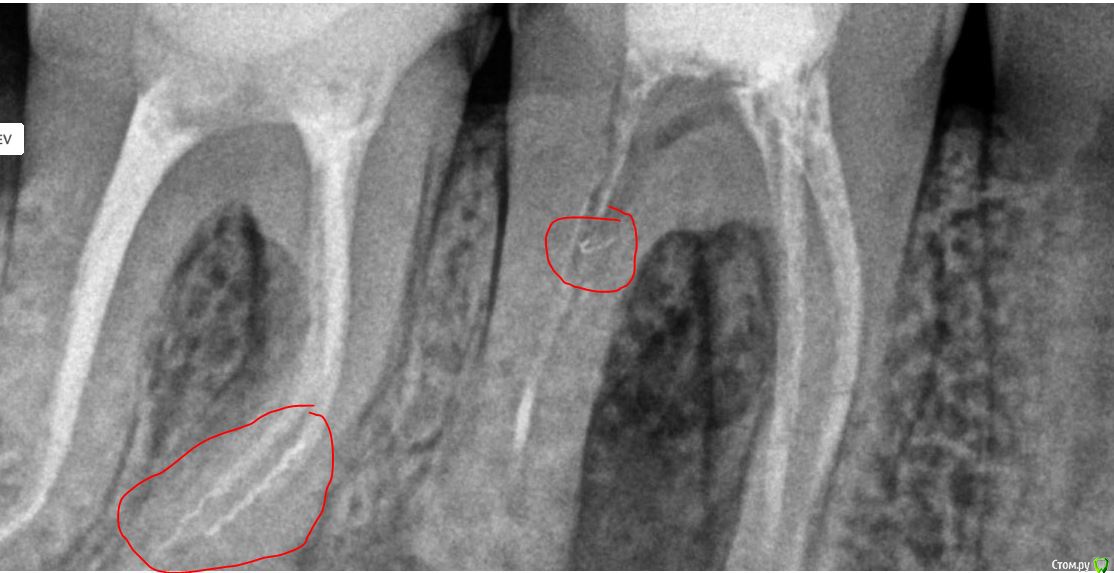

Bibika2020 Опубликовано 1 июня, 2020 Автор Поделиться Опубликовано 1 июня, 2020 (изменено) Вот ещё на снимке смущает (обвёл красным):1. на правых корнях 7го зуба волнистые линии это не остатки инструмента?2. непонятная загагулина на проблемном канале 6го зуба. что это может быть ? А что означает раскрытие полости зуба? Это его рассверливание, чтобы легче было к каналу доступ осуществить? Изменено 1 июня, 2020 пользователем Bibika2020 Ссылка на комментарий

dok1 Опубликовано 1 июня, 2020 Поделиться Опубликовано 1 июня, 2020 Щестёрка с булавоообразным утолщением корня. Пошла резорбция апекса. Плюс резорбция в просвете каналов. Я в шестой неверю . По этому бы рекомендовал удалить. Седьмой, если удастся извлечь инструмент, можно вылечить Ссылка на комментарий

Kolchanov Опубликовано 1 июня, 2020 Поделиться Опубликовано 1 июня, 2020 Щестёрка с булавоообразным утолщением корня. Пошла резорбция апекса. Плюс резорбция в просвете каналов. Я в шестой неверю . По этому бы рекомендовал удалить. Седьмой, если удастся извлечь инструмент, можно вылечитьКлючевое слово - не верю. Все остальное ерунда. Ссылка на комментарий